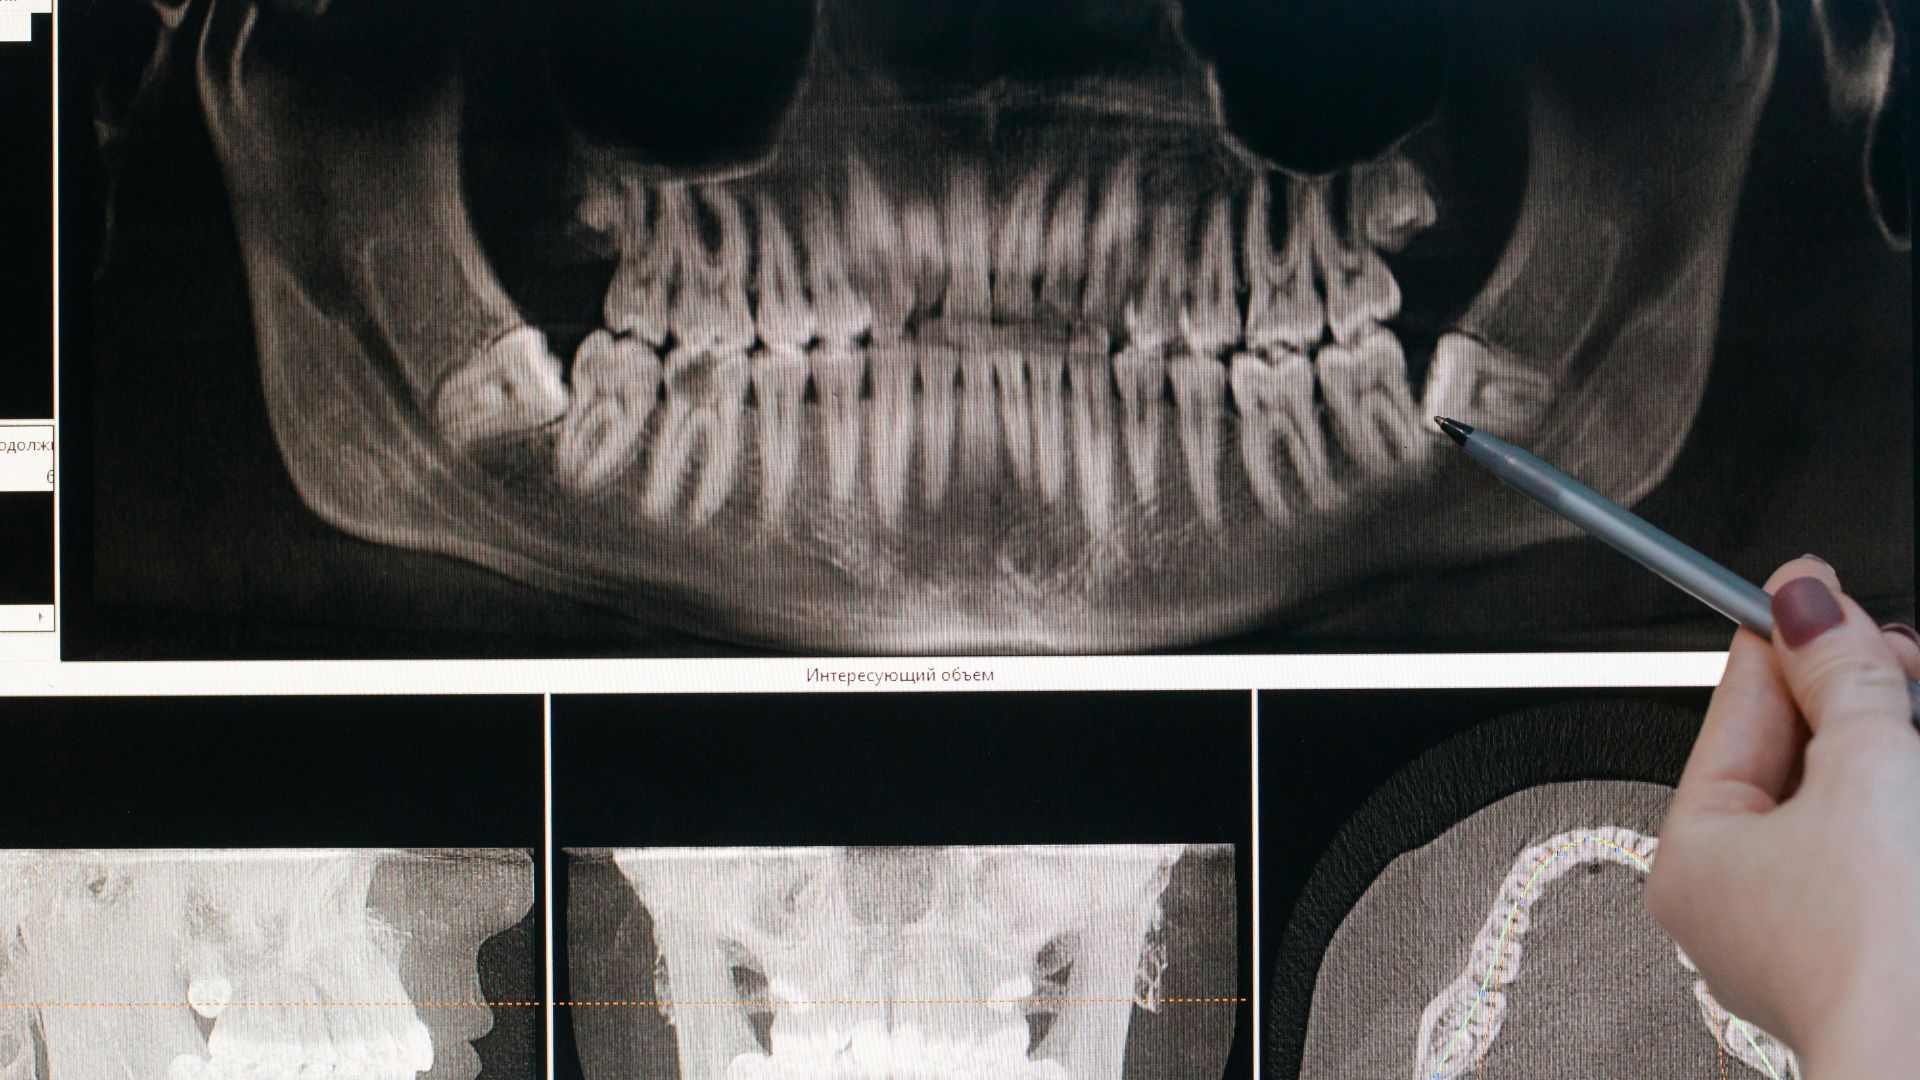

Diagnostyka zaburzeń stawu skroniowo-żuchwowego opiera się przede wszystkim na dokładnym wywiadzie i badaniu klinicznym. Lekarz ocenia zakres ruchu żuchwy, obecność dźwięków stawowych, bolesność mięśni oraz symetrię pracy obu stawów. Istotna jest także analiza zwarcia i stanu uzębienia.

W bardziej złożonych przypadkach pomocne bywają badania obrazowe. Rezonans magnetyczny pozwala ocenić położenie krążka stawowego i stan tkanek miękkich, natomiast tomografia komputerowa dostarcza informacji o strukturach kostnych. Dobór metody diagnostycznej zależy od charakteru objawów i ich nasilenia.